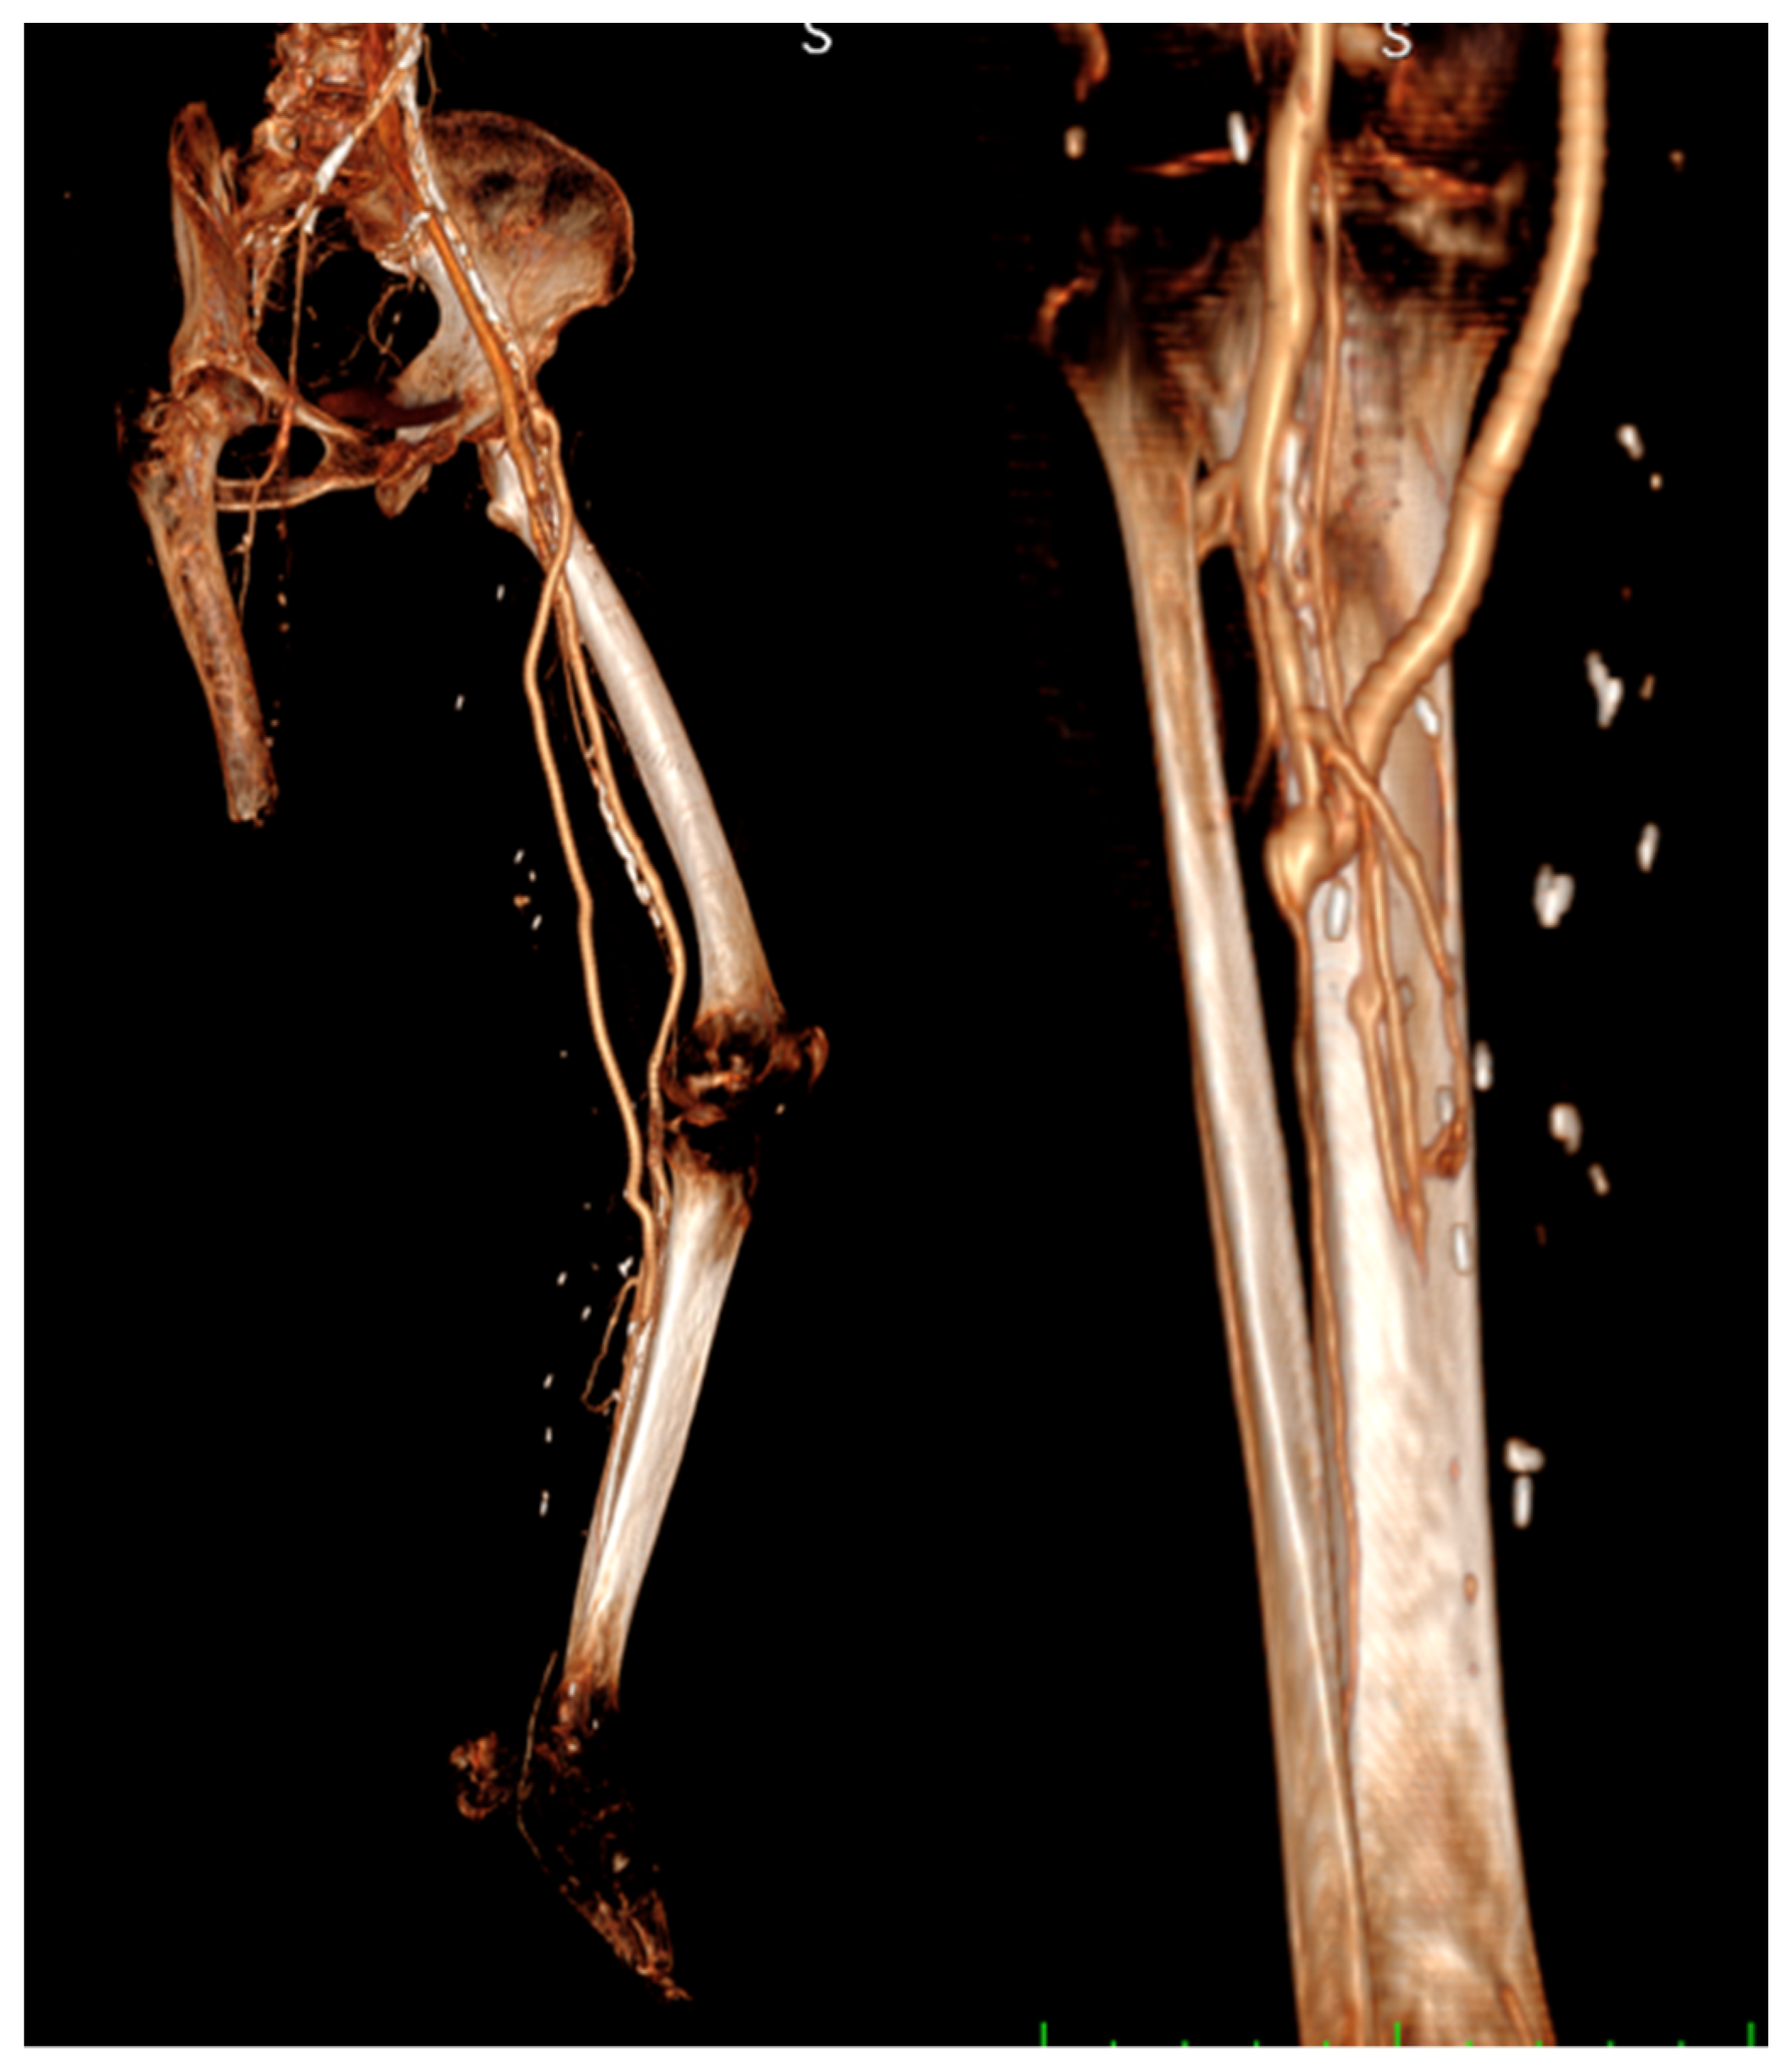

CT angiography was sometimes performed to show the bypass course (Figure 3).

Figure 3.

CT angiography.